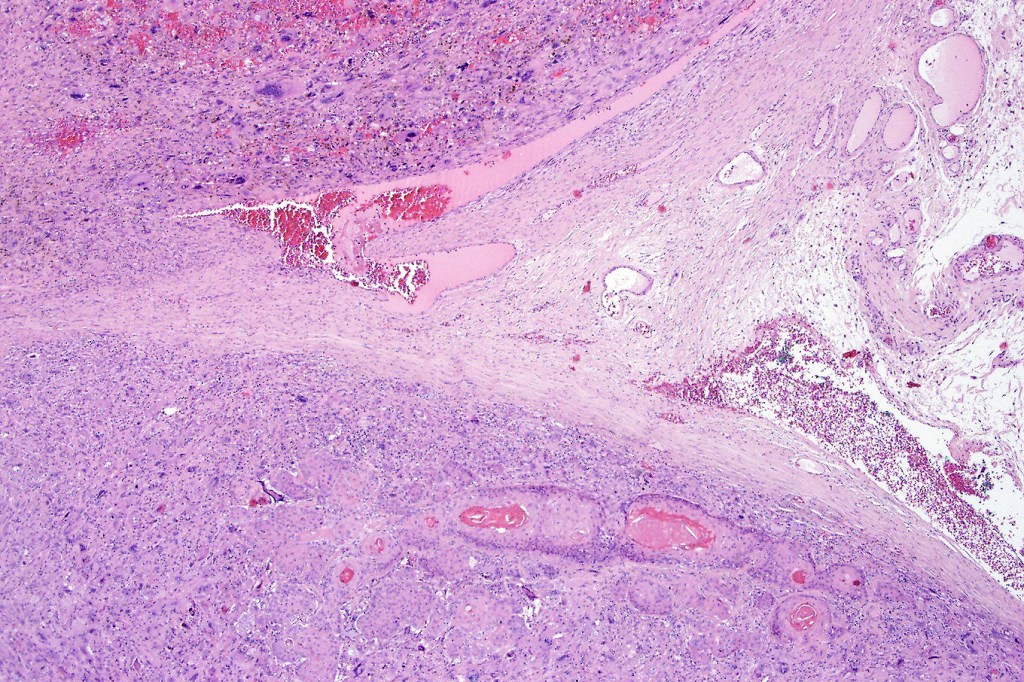

Carcinosarcoma

Cutaneous carcinosarcoma (metaplastic carcinoma, carcinoma with heterologous differentiation)

Histological features

•Osteoid

•Chondroid

•Smooth muscle

•MFH-like features with osteoclasts

•Neural differentiation